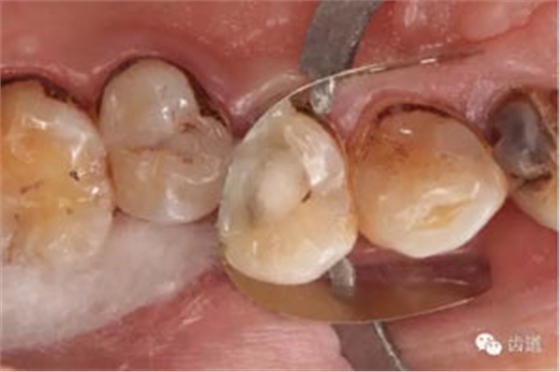

處理:放置橡皮障,去除暫封,超聲結(jié)合2%CHX清除遠頰根管內(nèi)氫氧化鈣糊劑,主牙膠試合后95%酒精沖洗干燥根管,結(jié)合AHPlus糊劑連續(xù)波熱牙膠垂直加壓充填根管,樹脂分層粘接修復牙體。建議定時復診進行嵌體修復,患者未執(zhí)行。